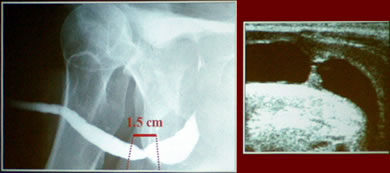

Короткие

посттравматические стриктуры